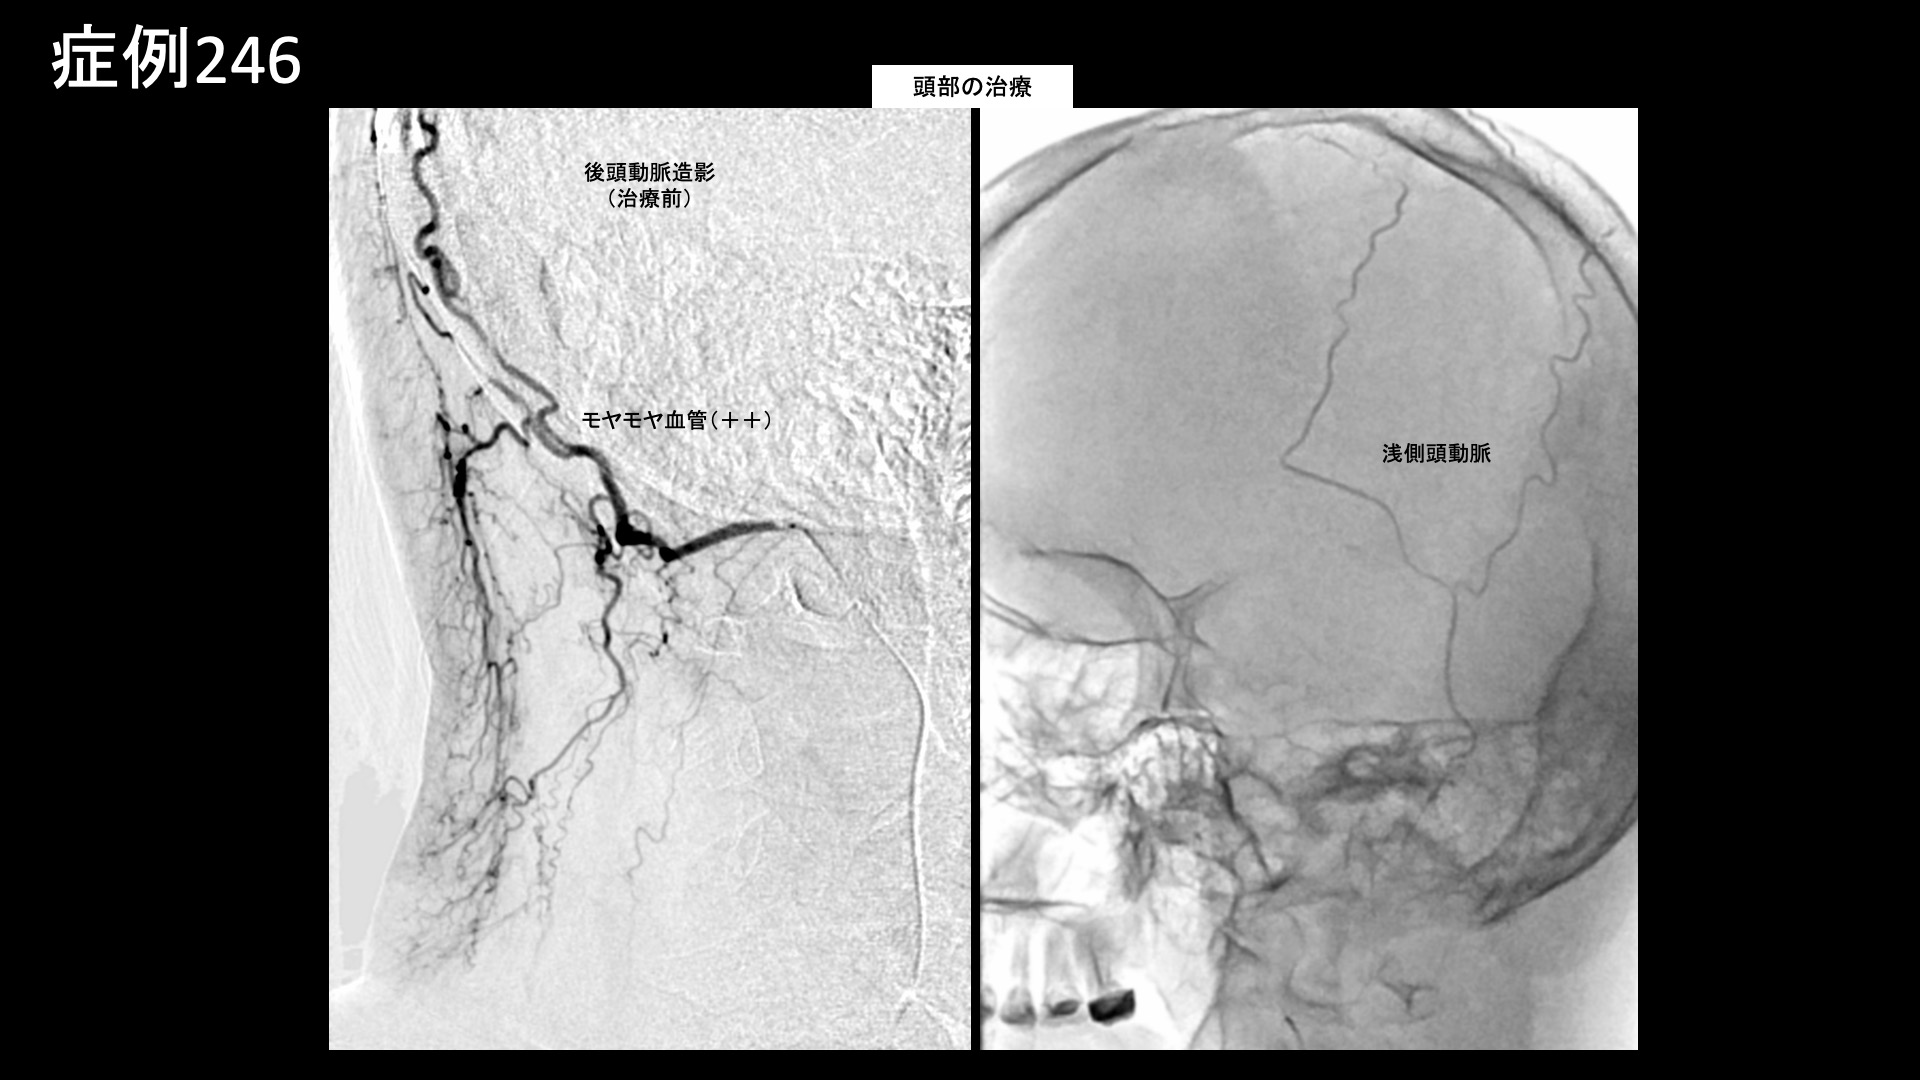

治療の所見

まず首肩こりの治療を行いました。血管造影を行うと、首こりの主要責任血管である深頸動脈、上行頸動脈筋肉枝などでモヤモヤ血管が濃染像として描出されました。肩こりの主要責任血管である頸横動脈、その他複数個所の血管を治療した後、頭部・顔面の治療を行いました。特に、後頭動脈でモヤモヤ血管が濃染像として描出されました。いずれも治療後は画像上速やかに消失しました。その他複数箇所の治療を行い終了しました。